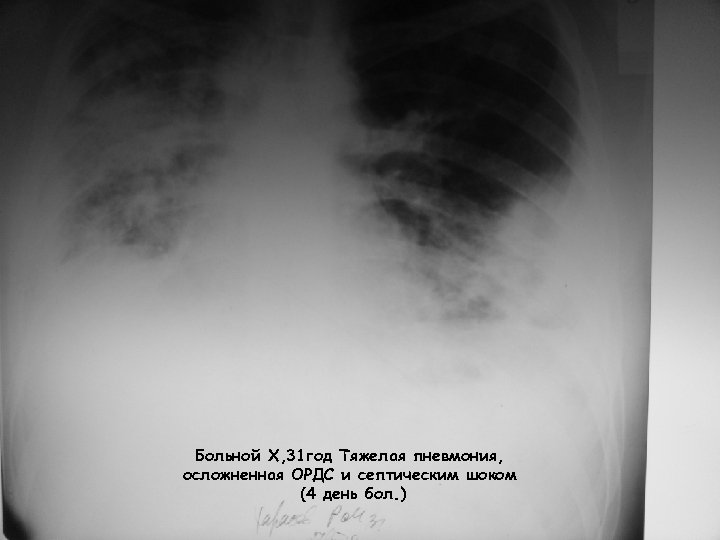

Больной Х, 31 год Тяжелая пневмония, осложненная ОРДС и септическим шоком (4 день бол. )